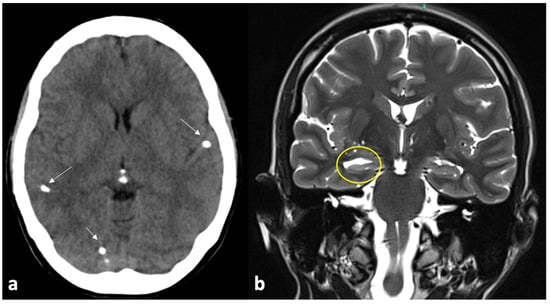

- Carrillo Mezo, R.; Lara García, J.; Arroyo, M.; Fleury, A. Relevance of 3D Magnetic Resonance Imaging Sequences in Diagnosing Basal Subarachnoid Neurocysticercosis. Acta Trop. 2015, 152, 60–65. [Google Scholar] [CrossRef] [PubMed]

- Citow, J.S.; Johnson, J.P.; McBride, D.Q.; Ammirati, M. Imaging Features and Surgery-Related Outcomes in Intraventricular Neurocysticercosis. Neurosurg. Focus 2002, 12, e6. [Google Scholar] [CrossRef] [PubMed]

- Bazan, R.; Hamamoto Filho, P.T.; Luvizutto, G.J.; Nunes, H.R.C.; Odashima, N.S.; Dos Santos, A.C.; Elias Júnior, J.; Zanini, M.A.; Fleury, A.; Takayanagui, O.M. Clinical Symptoms, Imaging Features and Cyst Distribution in the Cerebrospinal Fluid Compartments in Patients with Extraparenchymal Neurocysticercosis. PLoS Negl. Trop. Dis. 2016, 10, e0005115. [Google Scholar] [CrossRef] [PubMed]